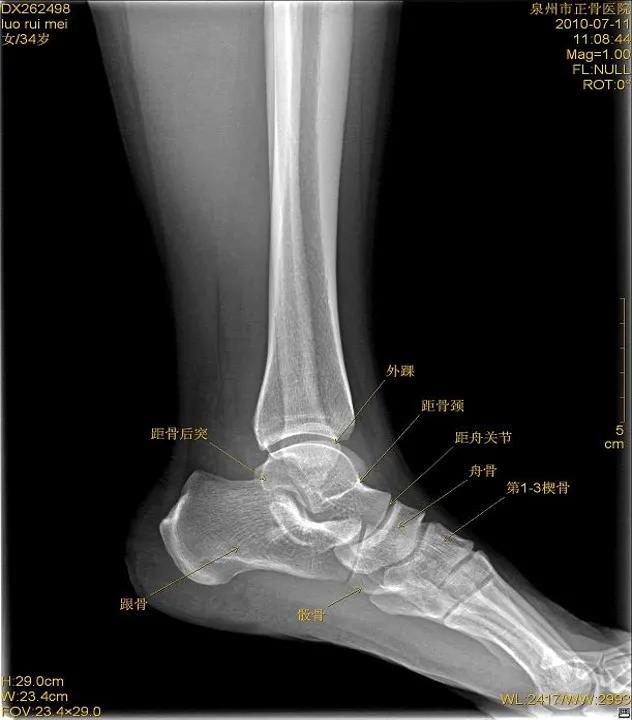

X线

踝关节正位

踝关节侧位